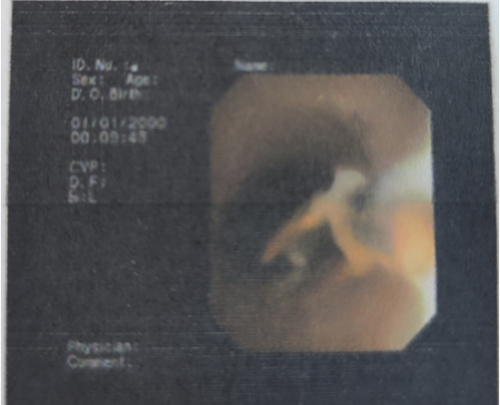

维多利亚老品牌76696vic全科医学科主任、主任医师肖智权接诊后仔细查看了王瑛的病历资料,完善肺部CT后显示其右下肺大片状阴影,建议该患者做纤维支气管镜检查。检查过程中,发现患者右肺下叶基底支有异物嵌顿,异物周围因滞留时间长已出现肉芽增生及大量脓性分泌物。内镜医师凭借经验和技术,操作纤维支气管镜的活检钳,将嵌顿的异物从患者右肺下叶基底支处完整取出,医生发现取出的异物竟然是一段辣椒尖。